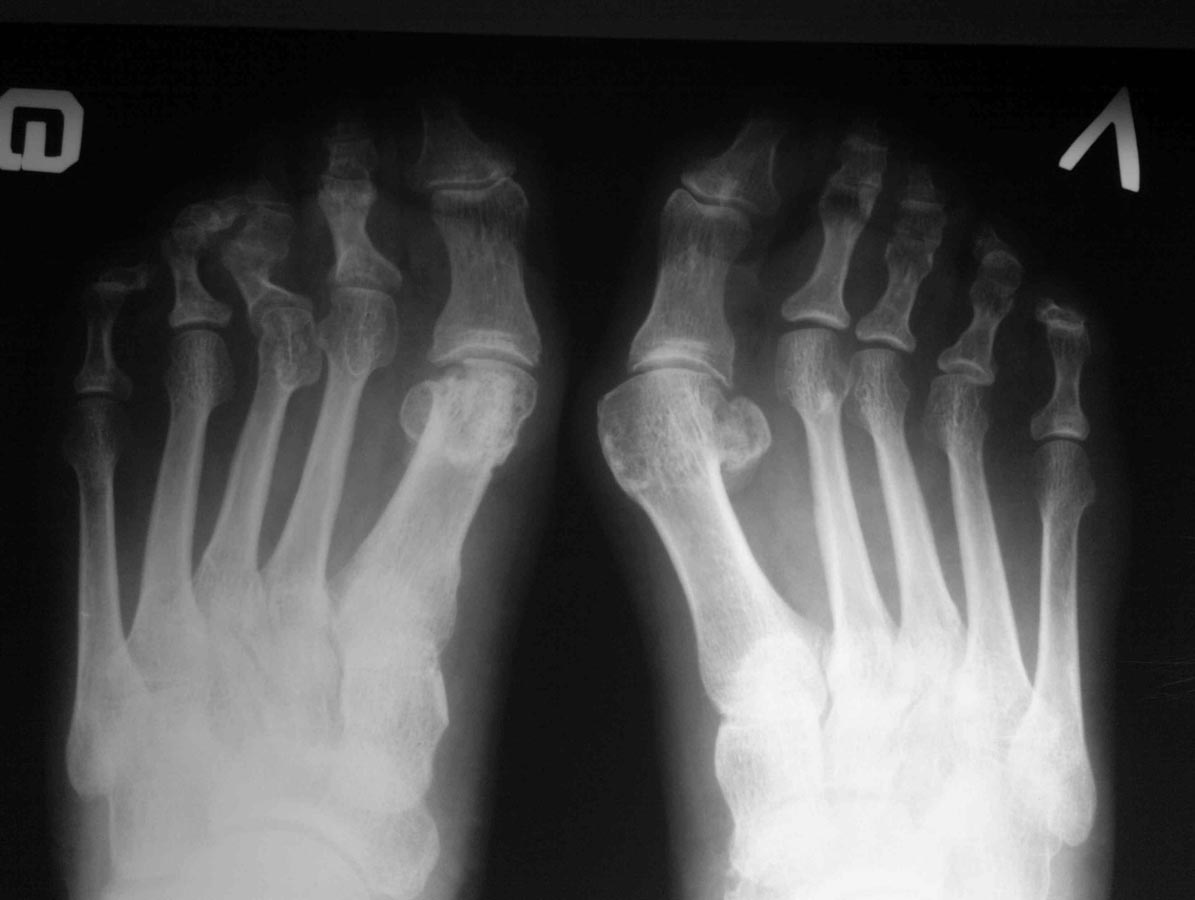

Укоротил 2-3, остеотомировал о/ф. Как-то так.

Очень адекватно. И необычный способ стабилизации 1 пальца. Все-таки после остеотомии Akin вполне достаточно укрепленной пластырем повязки.